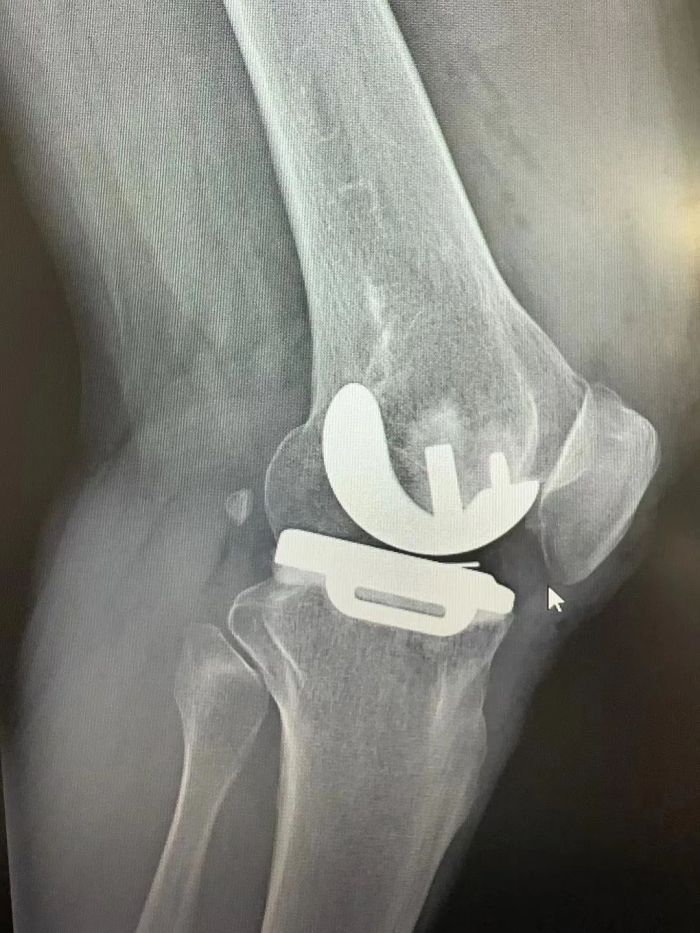

手术由吴韧教授指导、骨科一病区(关节、脊柱)行政主任易平主刀,术中医疗团队凭借精湛的技术和丰富的经验,精准地完成了每一个步骤。手术时间短,出血量少,术后患者状态良好。

术后患者膝关节情况